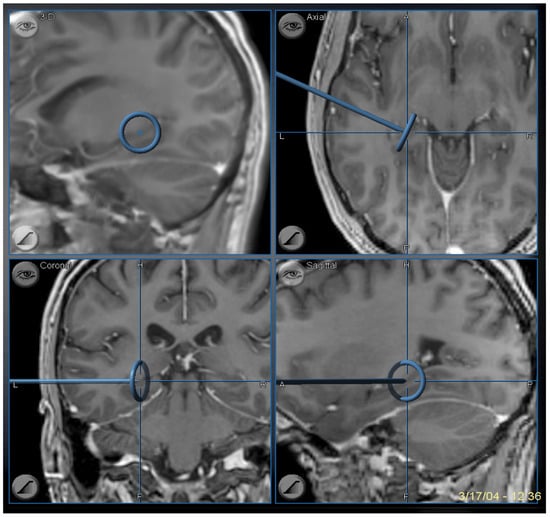

Figure 9.

Image guidance view of the navigation pointer at the posterior extent of the hippocampal removal, which corresponds to the level of the midbrain tectum.